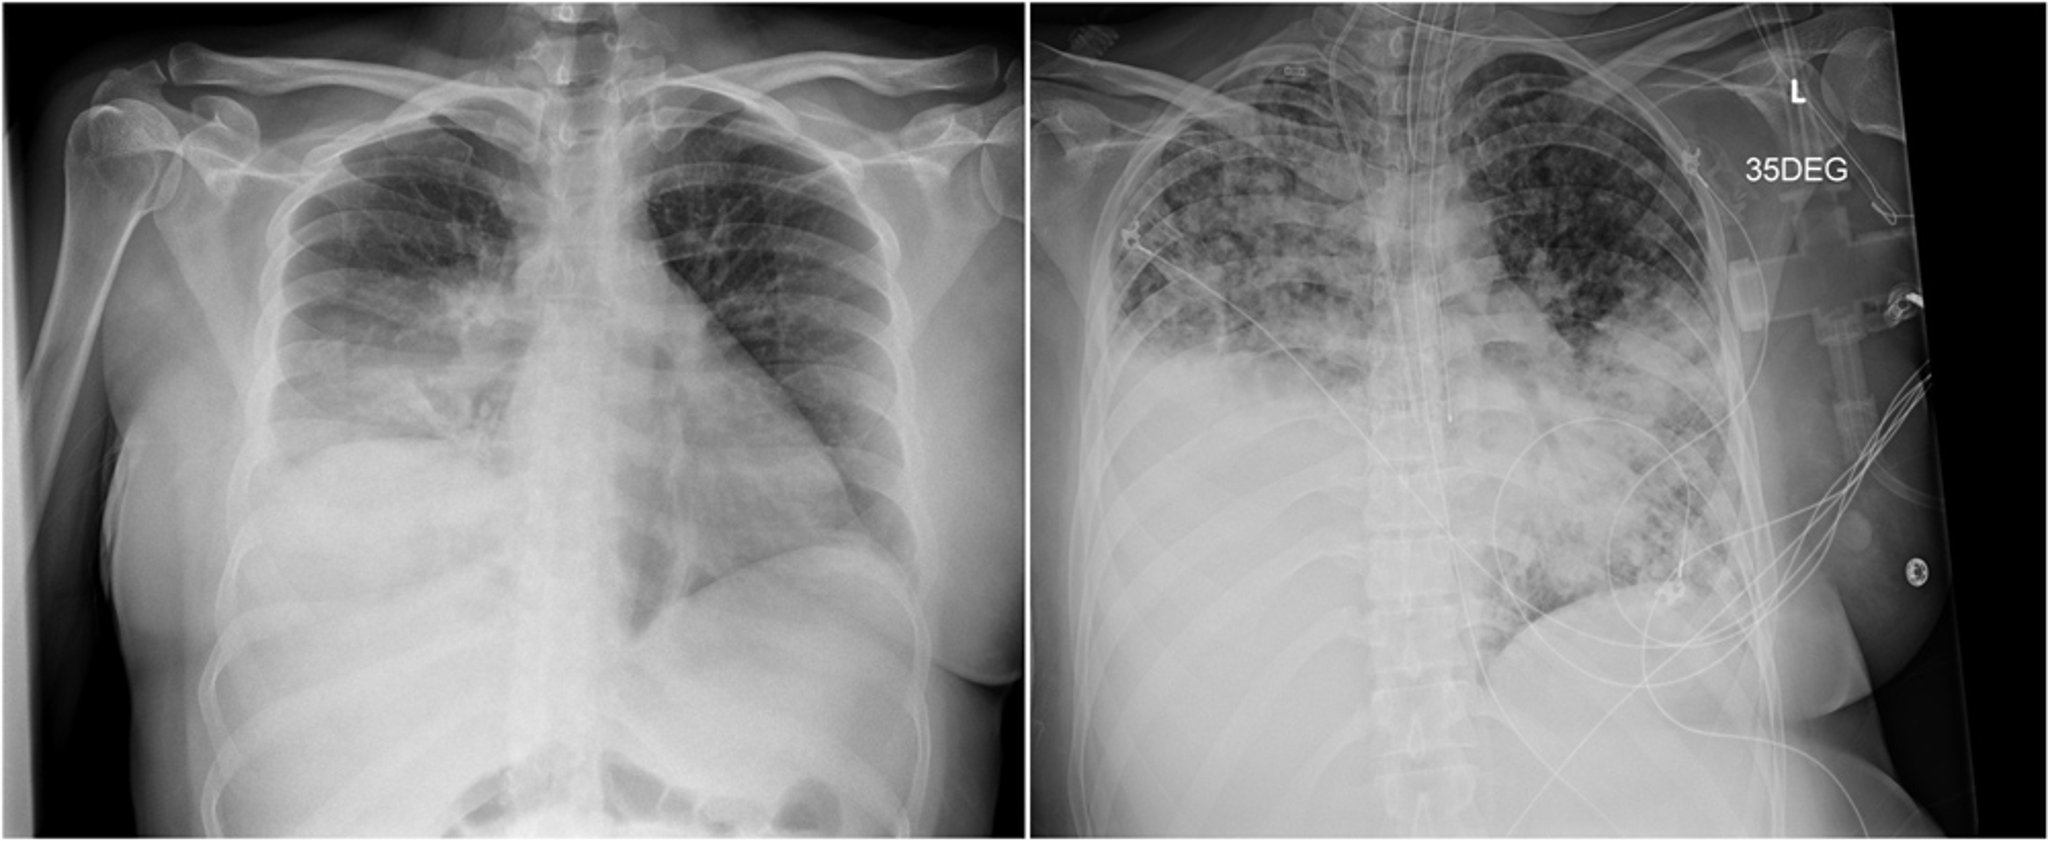

La radiografía de la izquierda muestra una consolidación del lóbulo inferior derecho que se confundió con una neumonía bacteriana. La radiografía de la derecha, tomada tres semanas después, muestra la progresión de la enfermedad con opacidades en el espacio aéreo bilateral en parches y consolidación densa en el lóbulo pulmonar inferior derecho.

Images courtesy of Paschalis Vergidis, MD, MSc.